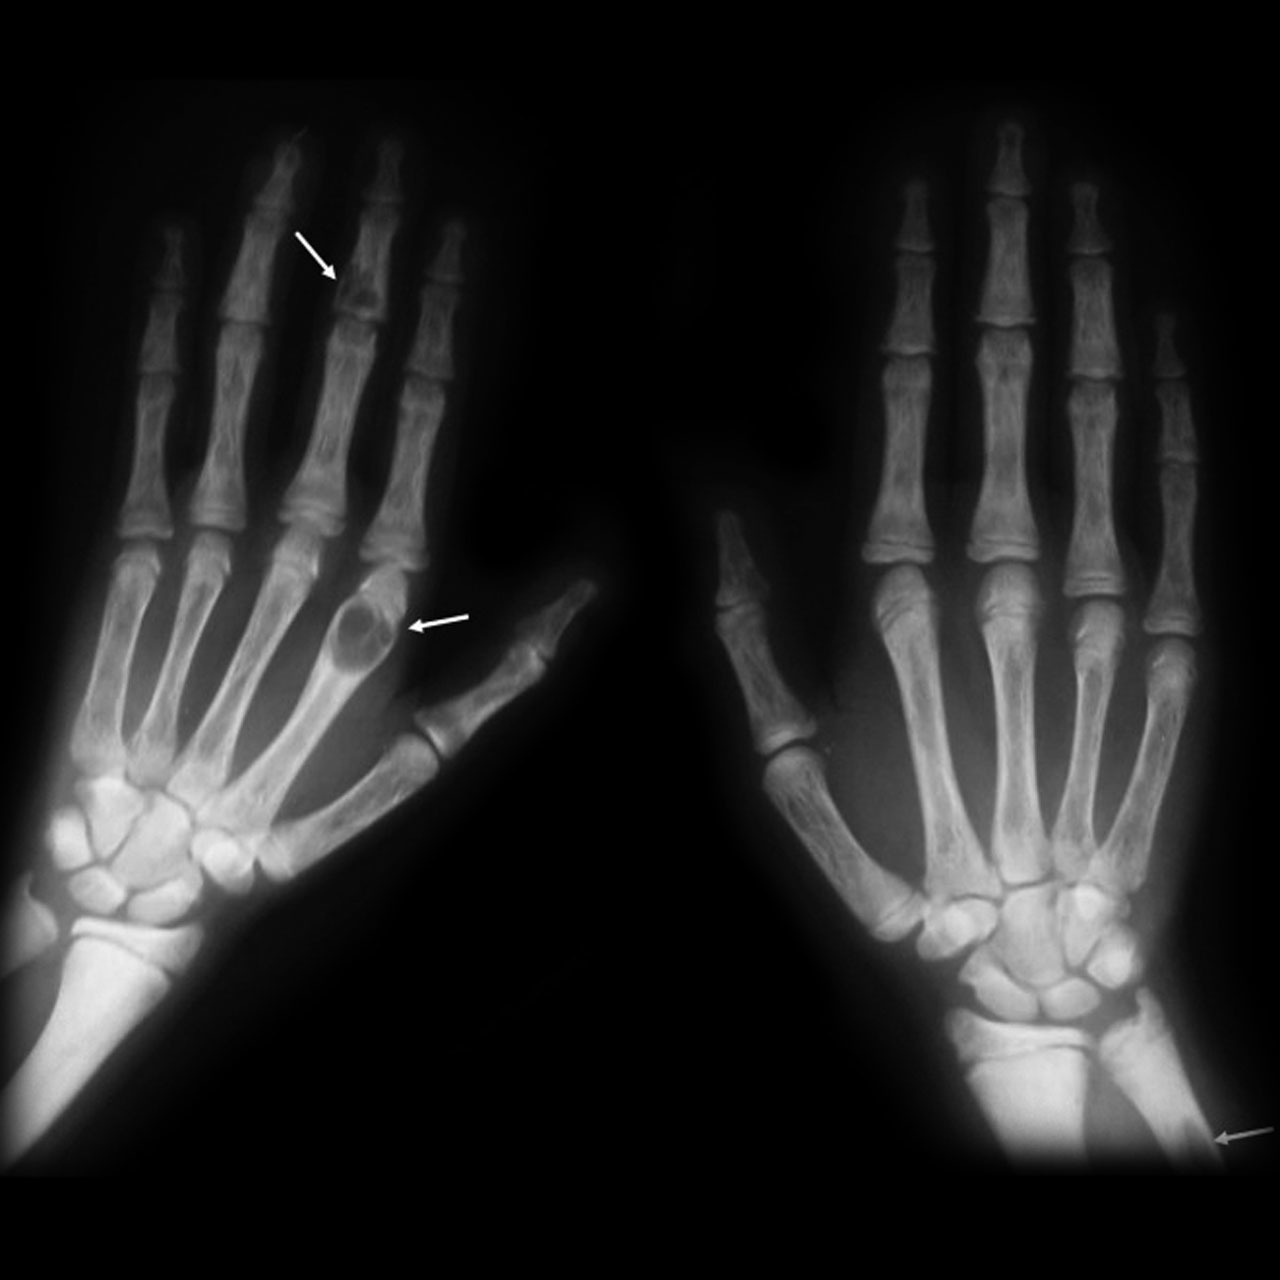

What does this patient with hyperparathyroidism present with?

Osteitis fibrosa cystica